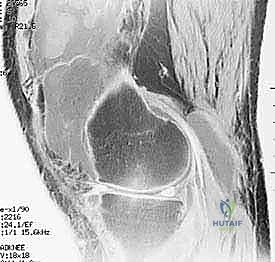

Magnetic Resonance Imaging (MRI) is invaluable for assessing the scope of joint involvement before surgery. It helps us differentiate localized from diffuse disease and visualize the extent of synovial hypertrophy. For instance, nodular PVNS can be readily seen as low signal on both T1 and T2 images.

Here, fellows, you see a T2-weighted MRI revealing a large effusion, typical in a patient subsequently diagnosed with rheumatoid arthritis.

Another view of the T2-weighted MRI, highlighting the extensive synovial involvement.